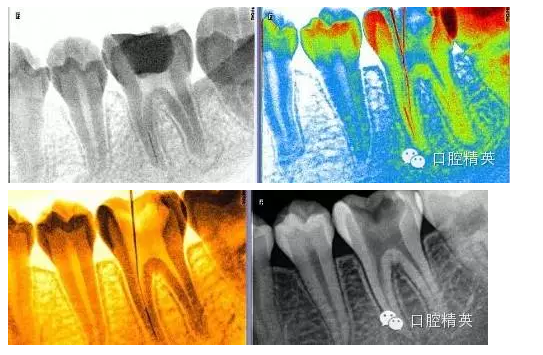

1,術(shù)前X-ray,常規(guī)術(shù)前攝片,

3,術(shù)前左下6近中根管斷針X-P,斷針長度約4MM,根尖慢性炎癥影像。。。

9,斷針取出術(shù)后X-P,RCT待續(xù)。。。